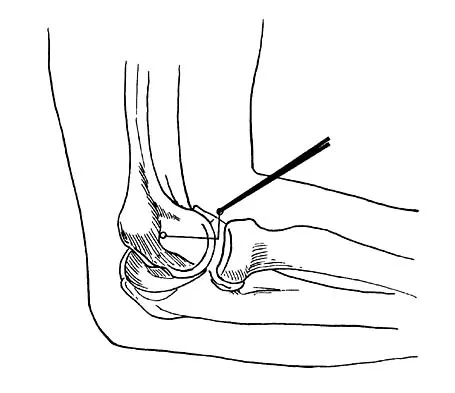

What nerve is at greatest risk of harm from the portal shown in Figure 36?